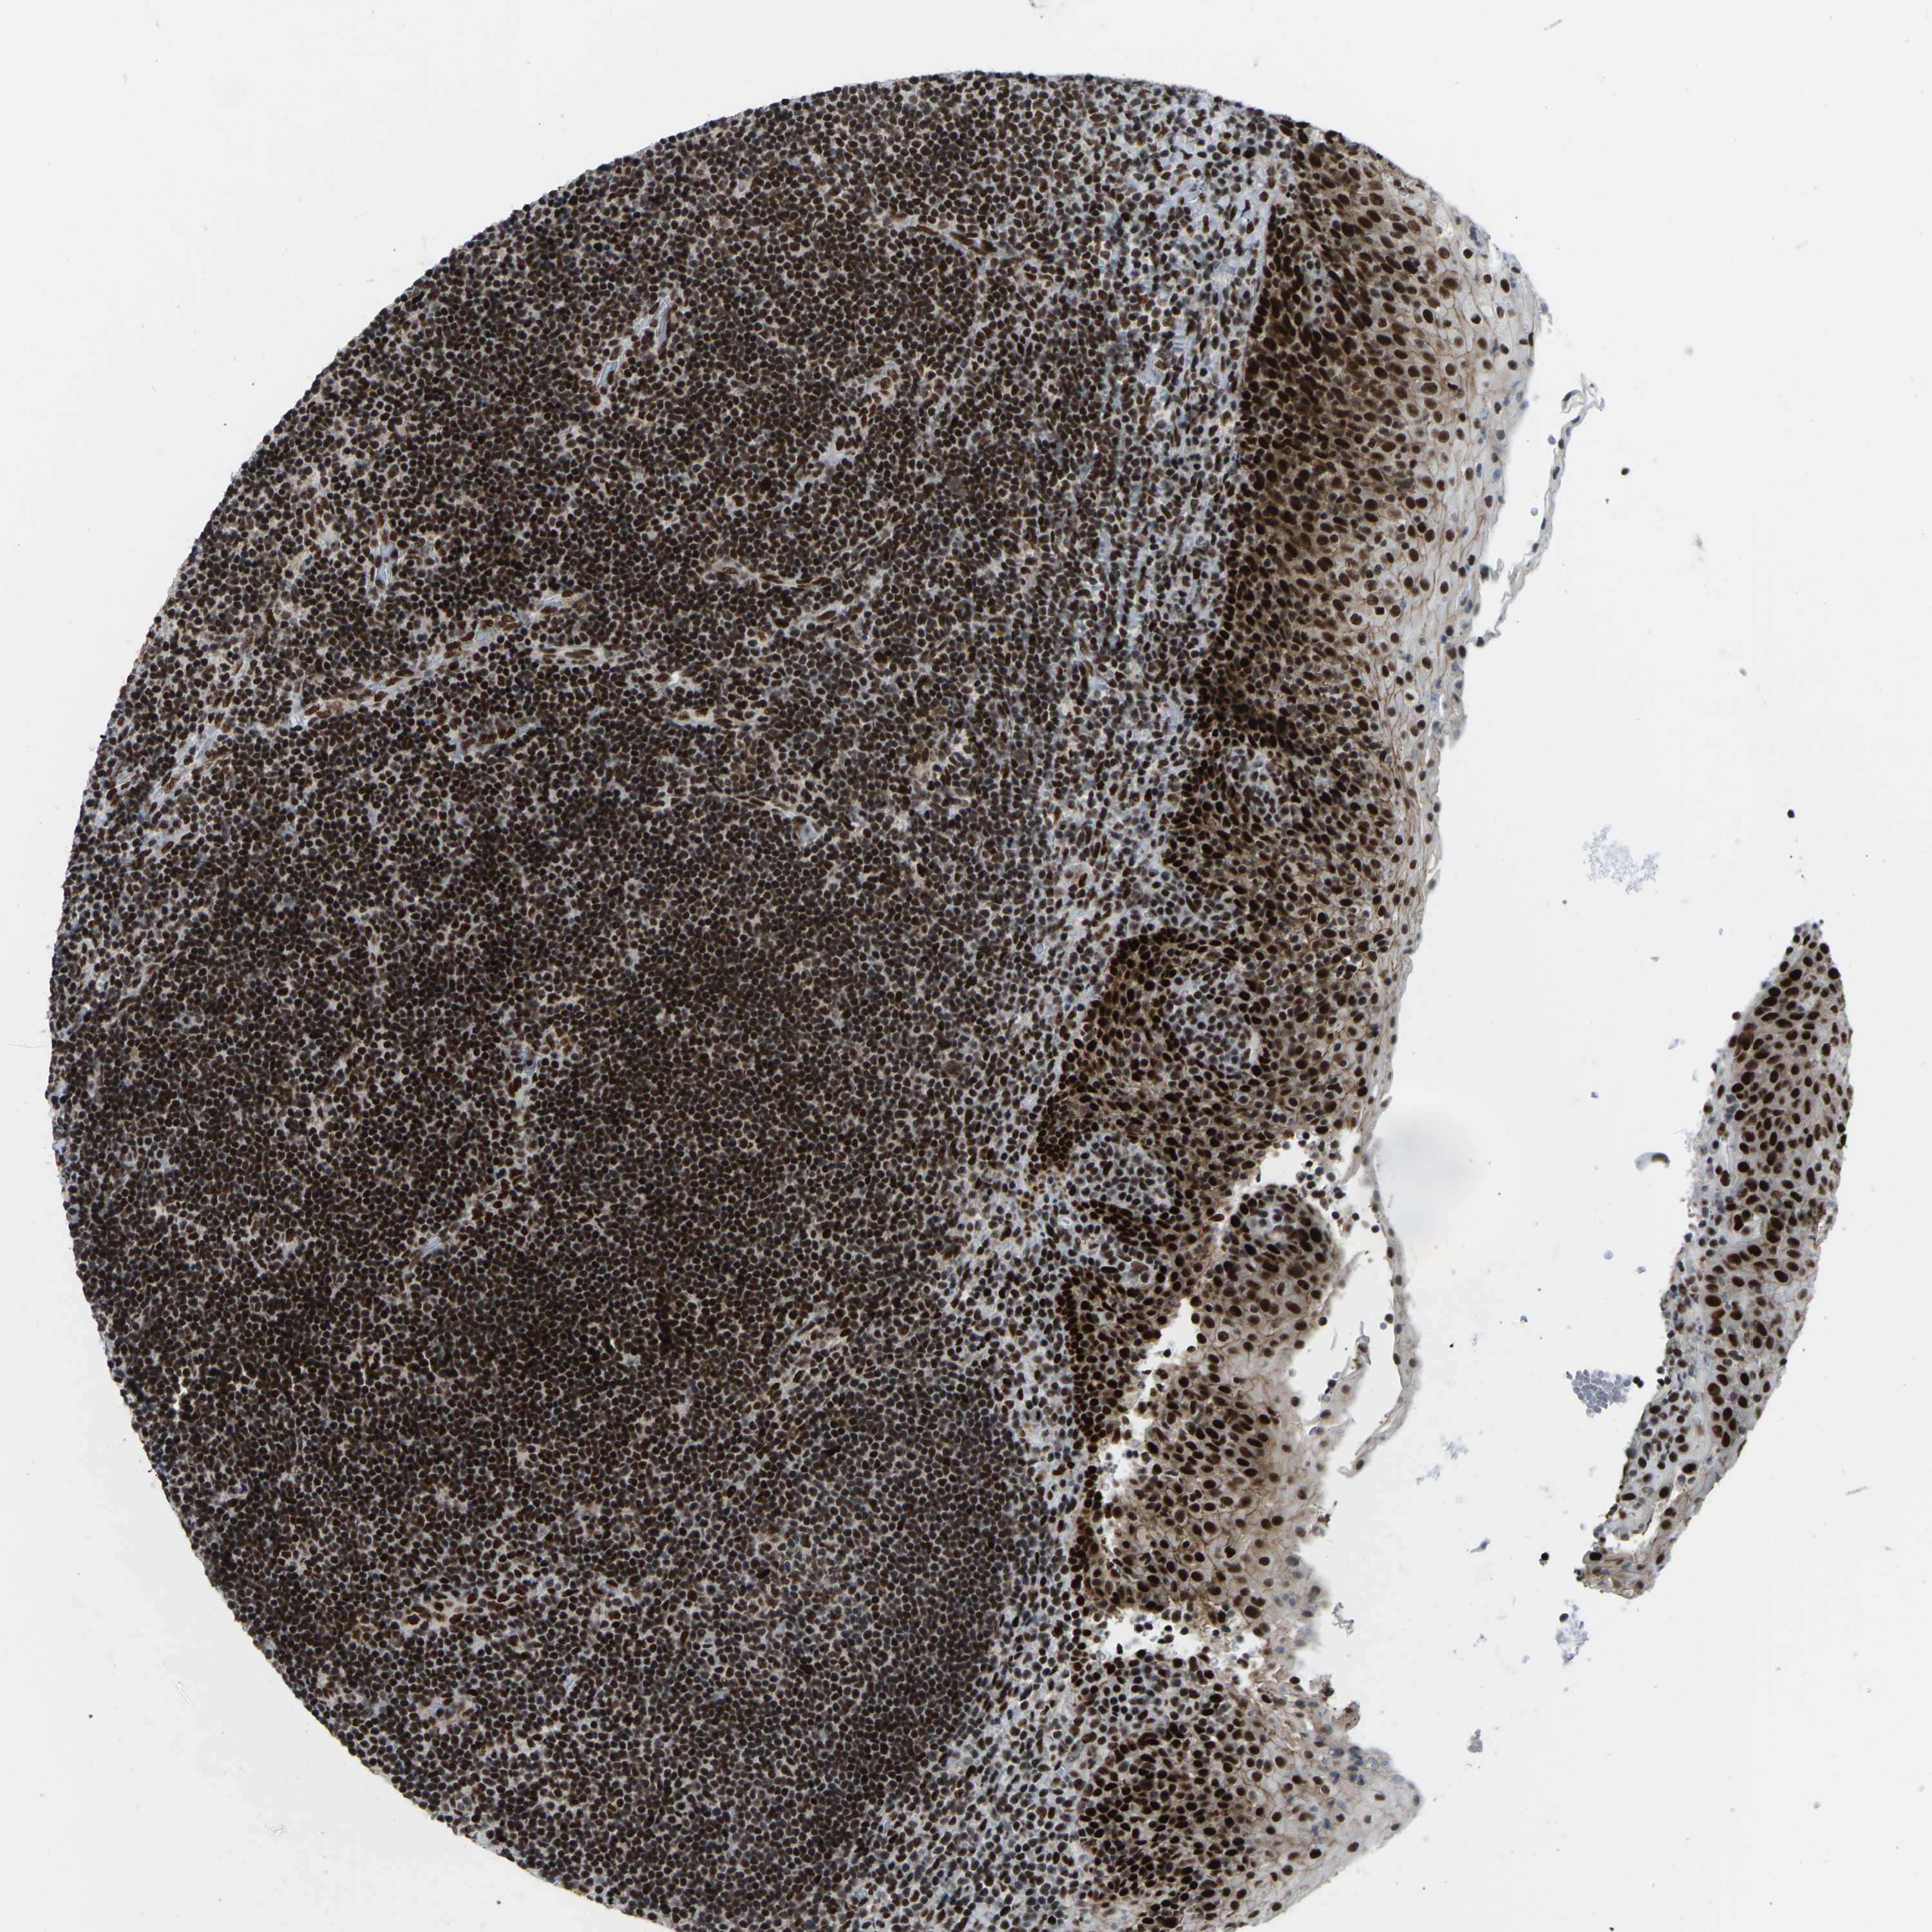

CANCER LYMPHOMA Show tissue menu

LYMPHOMA - Protein expressioni

A mouse-over function shows sample information and annotation data. Click on an image to view it in a full screen mode. Samples can be filtered based on level of antibody staining by selecting one or several of the following categories: high, medium, low and not detected. The assay and annotation is described here.

Each image is clickable and will lead to virtual microscopy that enables deeper exploration of all samples and also displays staining intensity scores, fraction scores and subcellular localization as well as patient and tissue information for each sample.

Antibody HPA017998

Hodgkin's disease, NOS

Malignant lymphoma, non-Hodgkin's type, High grade

Malignant lymphoma, non-Hodgkin's type, Low grade